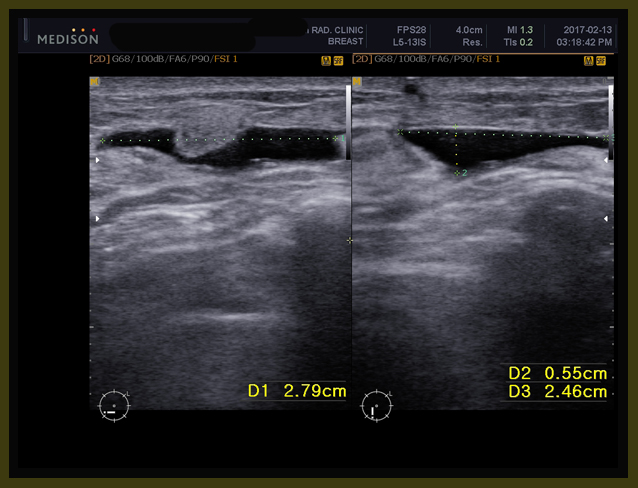

• 2015년 9월 유방암 발견  3.9 cm. 민간요법

• 2016년 2월 유방암 더욱 커짐  3.9cm  —-> 4.5 cm

• 2016년 2월 – 3월  #2차  AC  (adriamycin+cyclophosphamide) 요법 시행

• 2016년 3월 29일  본원 내원 종양  5cm 가량 약간 커졌음

• 2016년 4월 14일  본원  한약조치 이후  5cm의 종양  3.9 cm로 줄어들음

• 2016년 4월 15일  tamoxifen + 한방약물조치

• 2016년 5월 9일  1차  taxol  항암 시작함.  3.9cm(2016/4/4)  —-> 2.3cm (2016/5/26)

• 2016년 7월 8일  3차  taxol  항암 마침.  방사선 치료 의뢰

• 2016년 8월 – 9월 방사선 치료

• 2016년 9월 8일  2.3cm(2016/5/26) —-> 1.13cm(2016/9/8)

• 2016년 10월 13일 약 10mm  x 2mm의 종양의 괴사된 흔적 남아 보임

• 2017년 1월 16일 종양 완전소실  4.4×2.1mm의 흔적남음

• 2017년 5월 26일 초음파상 종양완전소실  2.4mm의 양성으로 보이는 흔적남음

• 수술 시행하지 않고 한약과 tamoxifen 요법을 지속함

이 환자는 2015년 9월 우측 유방에 약 3.9cm 가량의 종양을 발견하였다. 미혼인 이 환자는 유방암 발견 후에 당장 항암이나 수술을 결정하지 못하고 민간요법을 하면서 추이를 보았는데 5개월 뒤 종양은 3.9cm에서 4.5cm 정도로 자라 있었다. 2016년 2월 양방병원을 찾아 조직검사를 다시 하였고 당시 겨드랑이와 주변에 여러 개의 림프절이 보였는데 PET 상 악성으로 보여서 조직검사를 하였지만 다행히 림프절은 양성이 나왔고  main mass 외에 주변에 daughter nodule들이 몇 개 보였다.

주치의 선생님은 비록 양성이지만 여러 개의 림프절과 주위의 여러 개의 위성병변(satellite nodules)이 보이자 바로 수술하는 것보다는 항암으로 줄여서 하자고 하여서 태음인인 이 환자는 소음인에게 적합하다고 생각되는 AC 요법을  2차 하였다. 2차 후에 다니던 한의원의 권고로 본원에 내원하였는데

2월 11일부터 본원에 내원하여 3월 29일까지 종양의 초음파상 크기는 오히려 4.5cm에서 5cm 가량으로 커져 있었다. 환자의 동의를 얻어 먼저 한약치료를 해 보고 잘 줄면 내가 제시하는 방법대로 체질에 따른 항암 방법을 해 볼 것을 권유하였다. 본원의 한약 GO500을 사용하고 나서 보름 사이에 종양의 길이가 다시금 5cm에서 3 cm 정도로 빠른 감소를 보였다.

7-002

이 환자는 한방요법과  타목시펜 그리고 2차 택솔요법 이후에 초음파상에서 장경 3.9cm (2016/4/14)이 2.3 cm(2016/5/26) 이후 7월, 8월 사이에  방사선 치료를 권하였다.